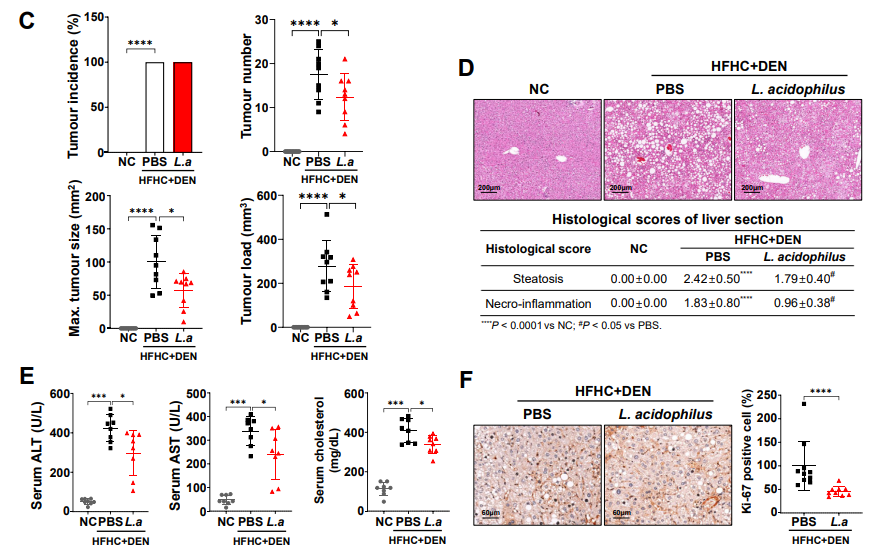

随着介入治疗技术的不断进步,经动脉化疗栓塞(TACE)被公认为最常用的肝癌非手术治疗方法。

61.9%的肝癌实施介入治疗。

TACE占介入治疗方式的91.44%。

TACE治疗HCC面临的

局限性与挑战

局限性

挑战

●复发、转移可能;

●远期疗效有限,5年生存率欠佳,一般在5~15%之间;

●需要联合其它治疗(分子靶向、免疫等)。